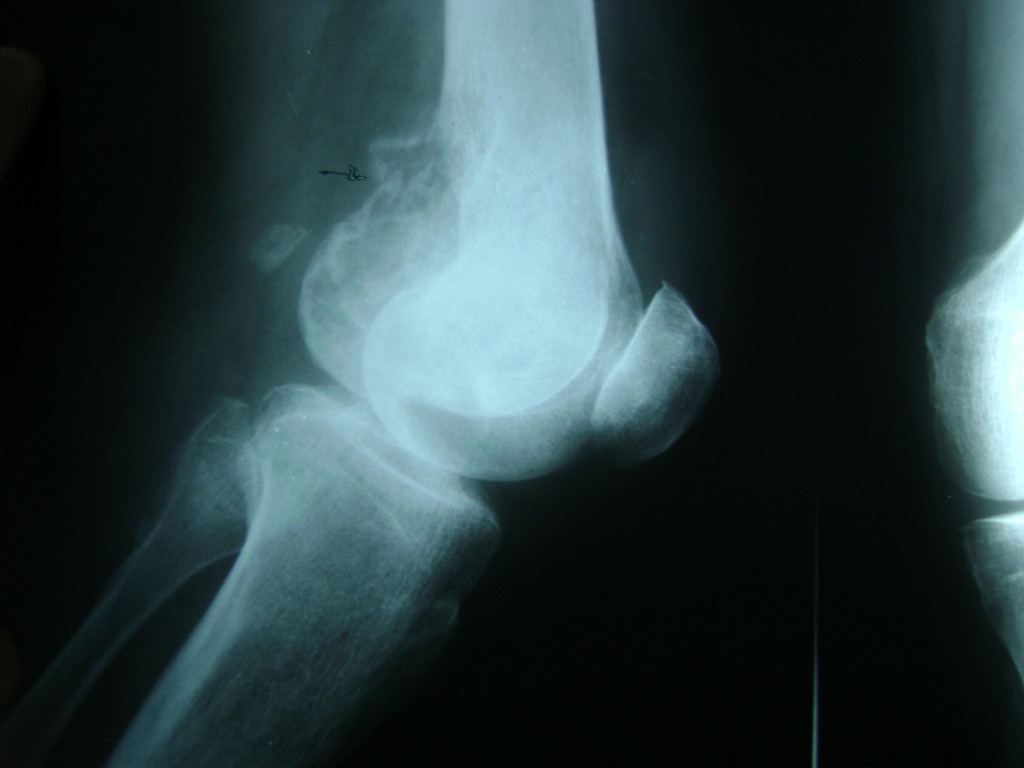

Cirugía de Rodillas